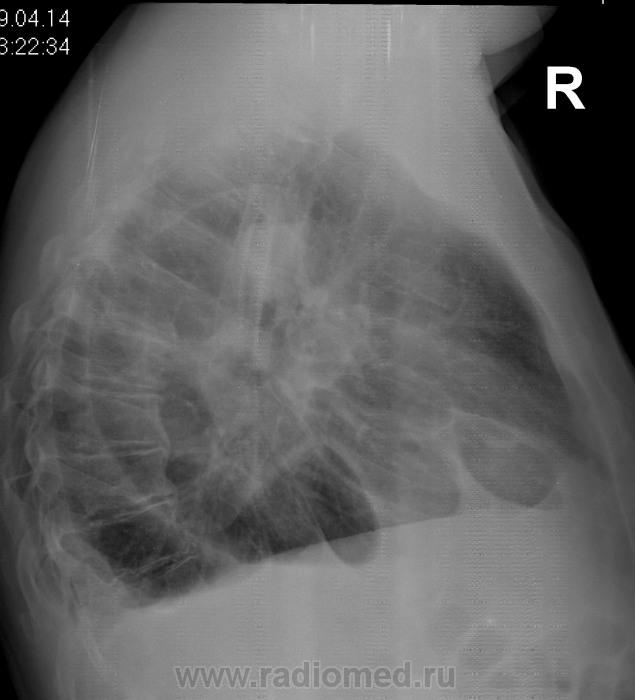

Какие мнения будут по снимкам уважаемые коллеги?

Ну очень осторожно:кишечные дела?

Хочется это явление назвать передней парастернальной диафрагмальной грыжей.

Медиастинальная грыжа. КТ собираетесь проводить?

Пластика толстой кишкой вместо удаленного пищевода по поводу рака.

Возможно швы на диафрагме оказались несостоятельными, и доктор не считает повторную операцию возможной.

Интересно, а полость перикарда как?